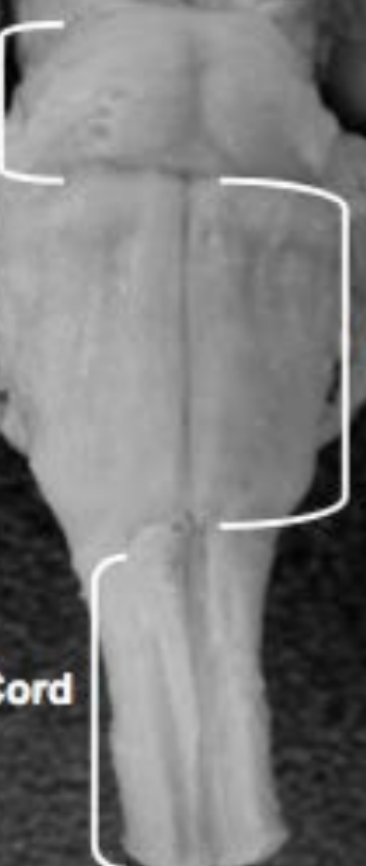

Pons

A

Medulla

Spinal cord

Voluntary movement, pain, sensation